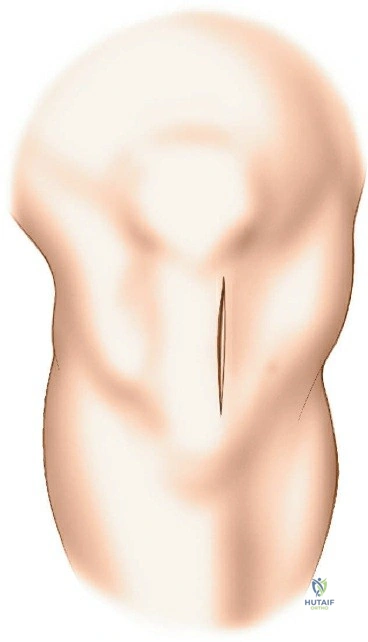

Patient Positioning

-

Supine on a Traction Table:

- Setup: The patient is placed supine on a radiolucent operating table. The affected hip is flexed to approximately 60 degrees. A support is strategically placed behind the posterior aspect of the distal thigh to allow the knee to flex freely. Crucially, care must be taken to position this support well away from the popliteal fossa to avoid compression of the popliteal artery and vein, which can lead to neurovascular compromise or compartment syndrome. The knee is then flexed to 100 to 120 degrees. Traction is applied by strapping the patient's foot to the sole plate of the traction apparatus.